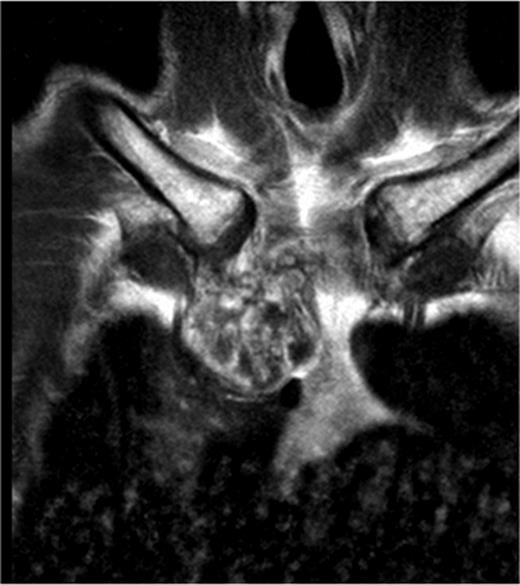

A 60-year-old male patient presented himself to the outpatient clinic of our department with a progressive sternal mass. An MRI scan indicated a tumour involving the manubrium extending to the first and second ribs and involving the right clavicle and sternoclavicular joint (Figs 1 and 2). Based on radiological evaluation, a core biopsy was obtained and a low-grade chondrosarcoma was characterized. Radiological evaluation indicated primary tumour resection to be the treatment of choice. Radical excision of the tumour was performed and resulted in resection of the manubrium, as well as the medial third of the right clavicle and the right first and second ribs. Steel wires through the sternum and left sternoclavicular joint spanned the 6.5 cm sternal defect (Figs 3 and 4) and a polypropylene mesh filled with methyl methacrylate composite (Surgical Simplex®), Howmedica Osteonics, Limerick, Ireland, was placed, yielding a stable reconstruction of the sternal defect (Figs 5–8). The sternocleidomatoideus muscle was re-inserted to the polypropylene mesh. Pathological examination showed complete excision of the tumour. The patient recovered uneventfully and was discharged 7 days post-operatively. At seven year follow-up, the patient displayed excellent functional and aesthetic results. Optimal function of his shoulders allowed a complete return to work and other activities without disabilities.

A MRI scan of a patient showing a tumour involving the manubrium extended to the first and second ribs including the right clavicle and sternoclavicular joint.